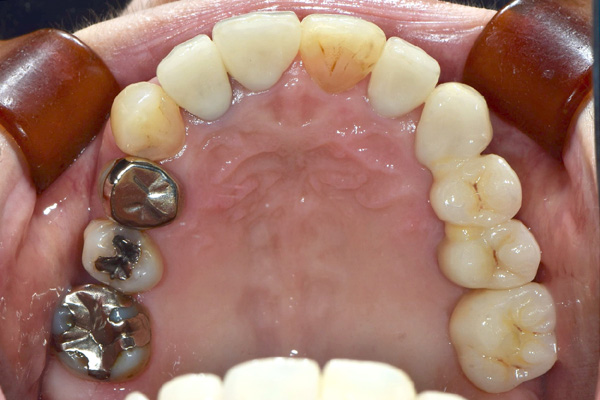

| 年代・性別 | 50代 男性 |

|---|---|

| 主訴 | 右上下の歯が痛い |

| 治療期間 | 約12ヶ月 |

| 費用 | 2,500,000円 |

| 治療内容 | インプラント、骨造成、結合組織移植、セラミック修復 |

| 治療に伴うリスク | インプラント周囲炎 セラミックの破折、脱離 |

*キャンセルポリシーをご一読のうえご予約ください